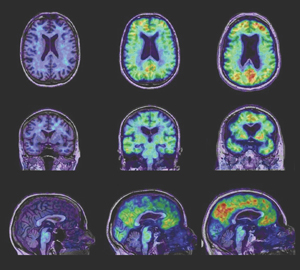

PiB-PET images show relatively low, non-specific, homogeneous PiB retention in white matter, while the variable retention in grey matter reflects fibrillar Aβ burden (Box). In patients with AD, high PiB retention can be readily visualised in the cortical mantle on inspection of images and, for the purposes of early detection and monitoring of progression, the advantages of quantitative measurements of Aβ deposition have been demonstrated.17 However, quantitative estimation of PiB binding is challenging and care must be taken to process the data correctly.

The first step is normalisation of the PiB signal to the signal in the cerebellar cortex, where PiB binding has been shown to be very low, reflecting an absence of dense Aβ deposition in that area. The resulting parameter is called the standardised uptake value ratio.18 The second important challenge is associated with the limited resolution of PET scans, which results in three issues when quantifying PiB images.

First, current PET camera resolution is low (~ 6 mm) compared with the thickness of the cortex (~ 3 mm), resulting in blurring or partial volume effect.19,20

Similar to atrophy patterns, PiB retention patterns can be computed, allowing a quantitative estimation of Aβ deposition at the voxel or regional level. Recent improvement in these techniques has revealed differences between grey matter atrophy and Aβ deposition patterns.20 Voxel-wise and regional correlation between PiB binding, atrophy, and other clinical measurements (eg, Mini-Mental State Examination score) have identified few relationships and only in specific brain areas. For example, the AIBL study has shown that hippocampal atrophy is correlated with PiB retention in the inferior temporal lobe only and not elsewhere, and only at the earliest stages of the disease in healthy, asymptomatic individuals with high PiB binding.13,21 However, it has also become clear from our studies that, while Aβ must be present for a diagnosis of AD to be made and it appears before atrophy and cognitive decline, there is not a direct, robust dose-dependent relationship between Aβ and cross-sectional measures of atrophy or measures of cognition, suggesting that other “downstream” factors are the predominant determinants of neurodegeneration.17,22 A more definitive understanding of the relationship of Aβ to neurodegeneration will emerge from the longitudinal findings of the AIBL study, which is currently in its third year of follow-up.